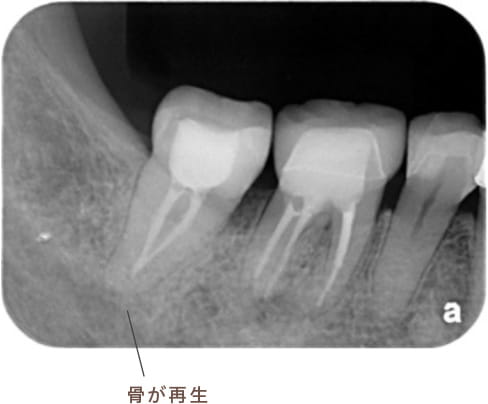

治療後病気がなくなり骨が再生した